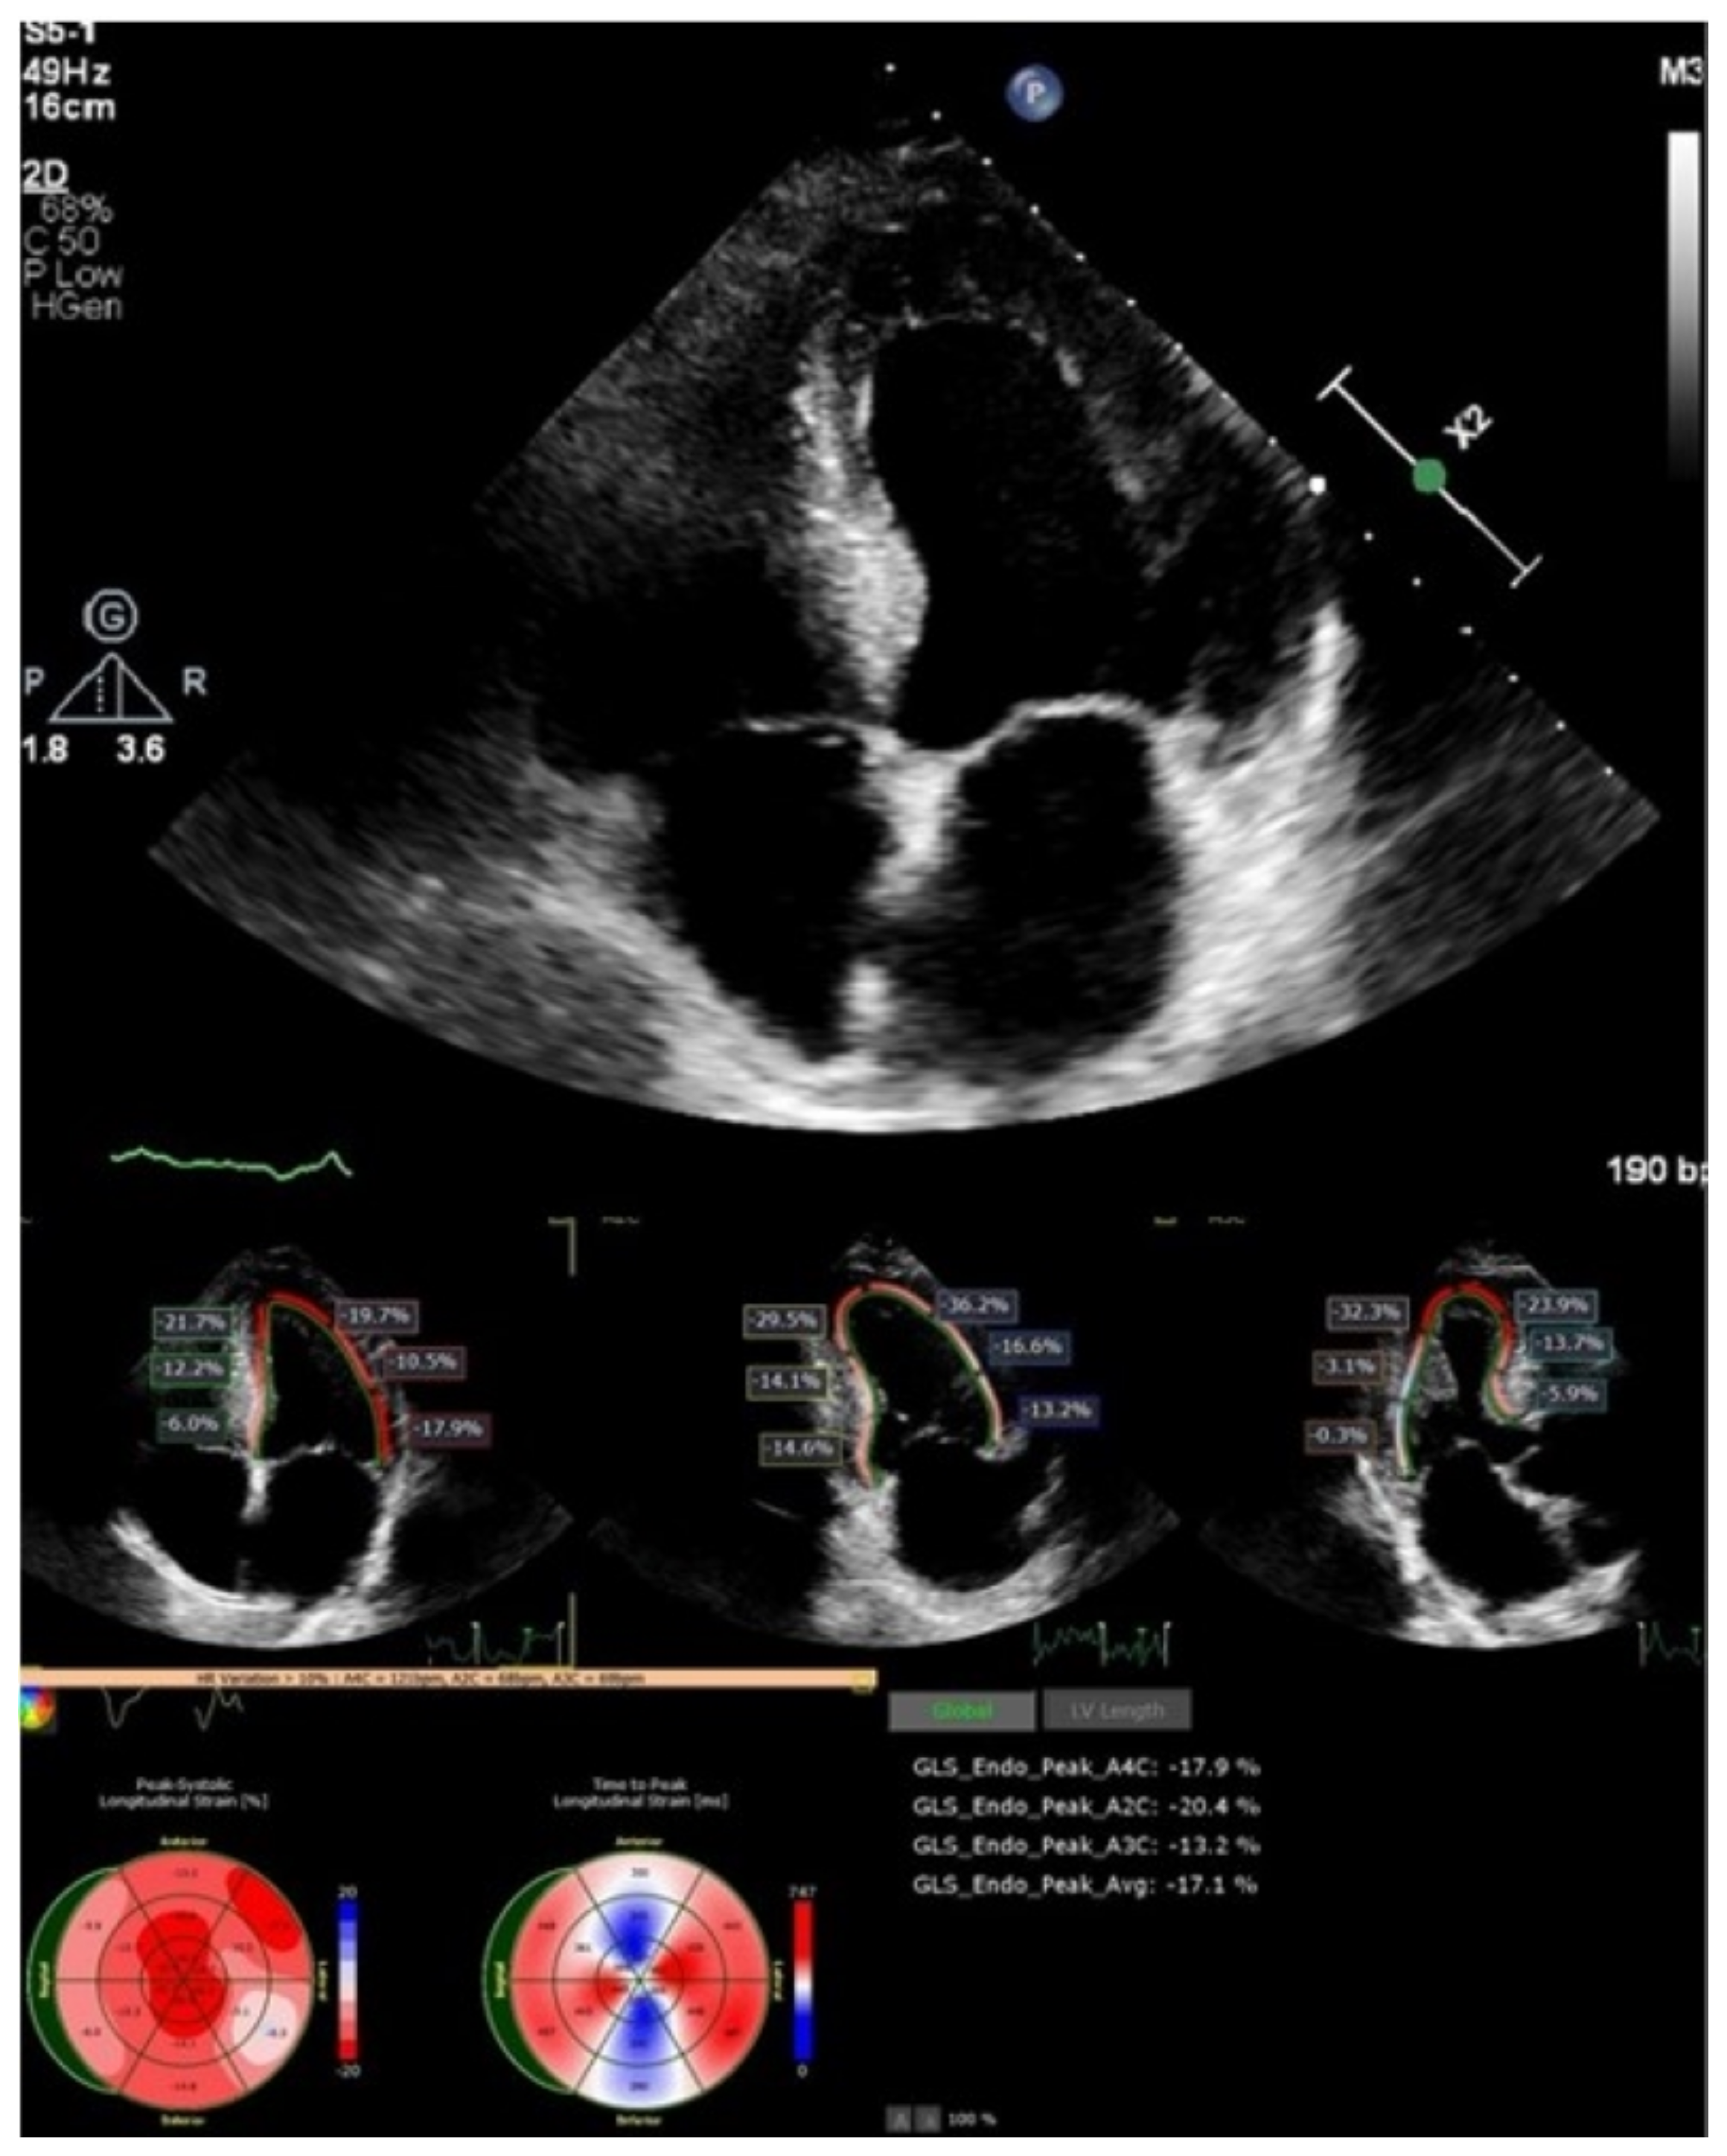

A two-dimensional echocardiographic examination (Figure 3) revealed left ventricle (LV) concentric hypertrophy without dilation, with preserved LV ejection fraction (LVEF of 60%) and pseudonormal diastolic dysfunction (E/E’—10, left atrial (LA) dilatation of 38 mL/m2), and reduced deformation LA parameters (left atrial reservoir strain of 22.3%). The global longitudinal LV strain was slightly reduced (−17%), with maintained strain values in the apical segments. The right-sided heart chambers were not dilated.

Figure 3.

Two-dimensional echocardiography and speckle tracking: LV hypertrophy with maintained strain in apical LV segments.